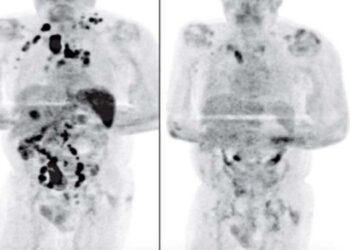

MUNDO| Um homem de 61 anos, teria sido curado de um linfoma de Hodgkin (um tipo de câncer que se origina ...